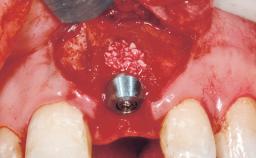

Late Placement of an Implant in a Maxillary Left Central Incisor Site

| Bone Augmentation | Horizontal|Staged |

| Augmentation Materials | Xenogenous|Membrane |

| Bone Volume | Deficient horizontally, requiring prior grafting |